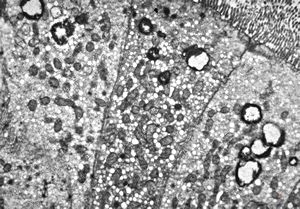

M,82y. | Helicobacter pylori - antrum ventriculi

M,82y. | Helicobacter pylori - stomach